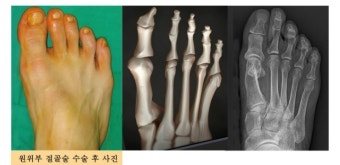

① 절골술 (Osteotomy)

- 가장 흔하게 시행되는 수술로, 뼈를 절단하여 재배열하는 방식입니다.

- 무지외반의 각도를 조절해 엄지발가락이 바르게 설 수 있도록 합니다.

- 금속 핀이나 나사로 고정한 뒤 시간이 지나면 제거하기도 합니다.